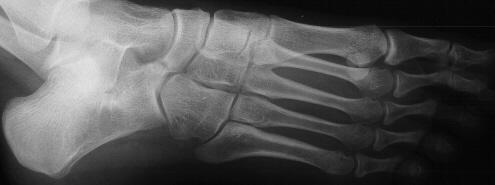

What x-ray is this?

What is the diagnosis?

45 degree oblique

Calcaneonavicular coalition